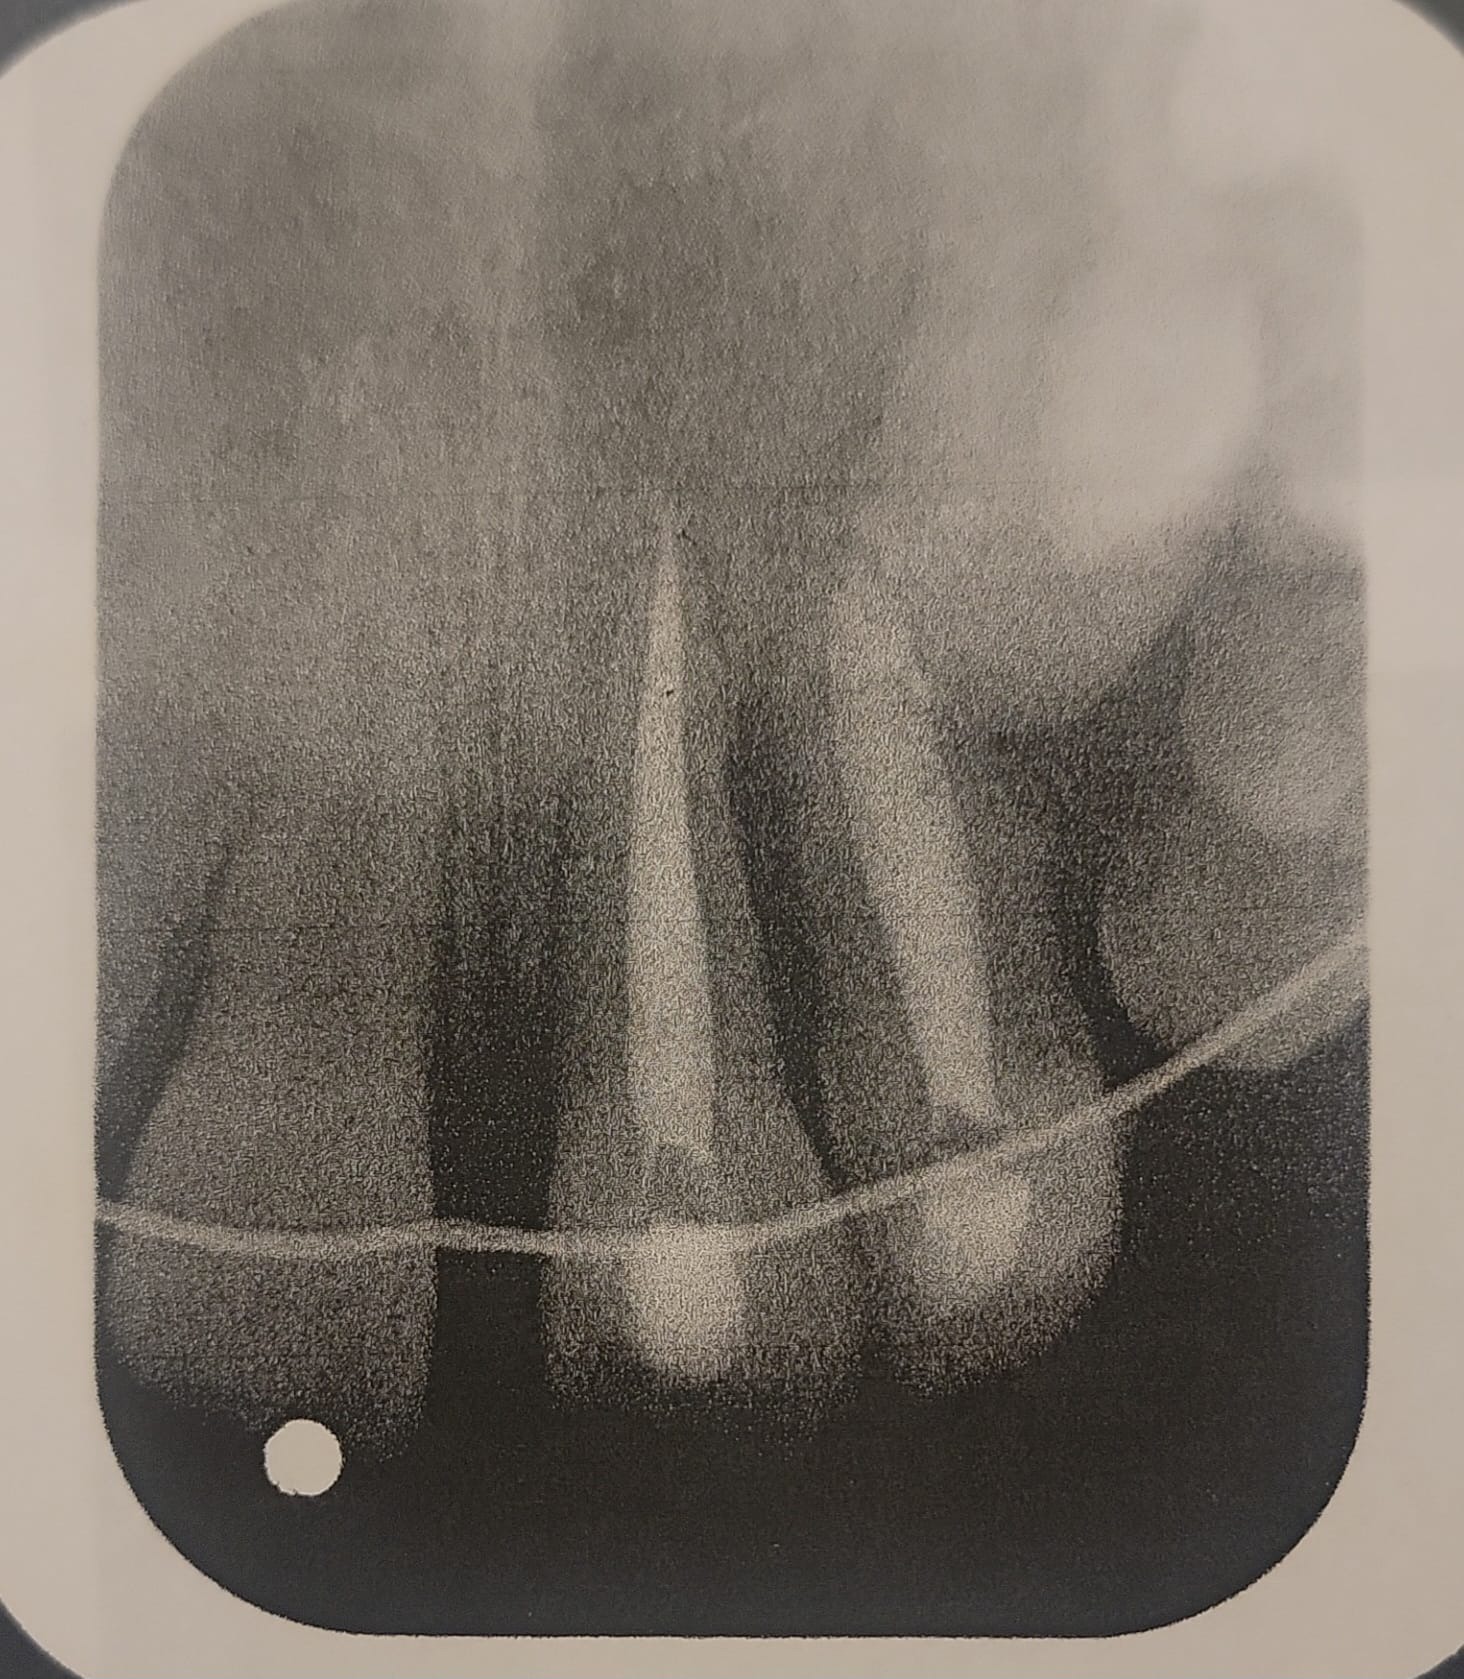

Hoy, con sus 18 años recién cumplidos, Liangelly finalmente puede someterse a los procedimientos médicos y dentales que necesita. Pero el tiempo ha pasado factura, y ahora enfrenta una serie de tratamientos complejos y costosos, incluyendo reconstrucción dental, injertos óseos y prótesis permanentes, además tiene un quiste y un abseso sobre un diente al cual se le realizó una biopsia y estamos en espera de los resultados.

Evaluaciones especializadas y radiografías 3D